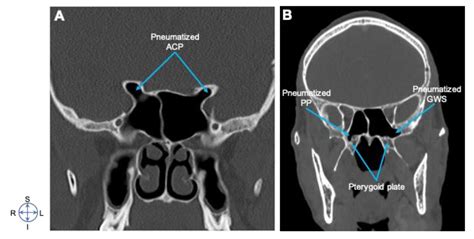

The sphenoid bone is a complex, butterfly-shaped bone situated at the base of the skull. It consists of several parts, including the body, lesser wings, and greater wings. The Greater Sphenoid Wing is the larger of the two wings and extends laterally from the body of the sphenoid bone. This wing is crucial for its role in forming part of the lateral wall of the skull and providing attachment sites for important muscles and ligaments.

• Foramina and Canals: The Greater Sphenoid Wing contains several foramina and canals that allow nerves and blood vessels to pass through. These include the foramen ovale, foramen spinosum, and the infraorbital groove.

• Computed Tomography (CT): CT scans provide detailed images of the bony structures, making them ideal for evaluating fractures, tumors, and other abnormalities in the Greater Sphenoid Wing.